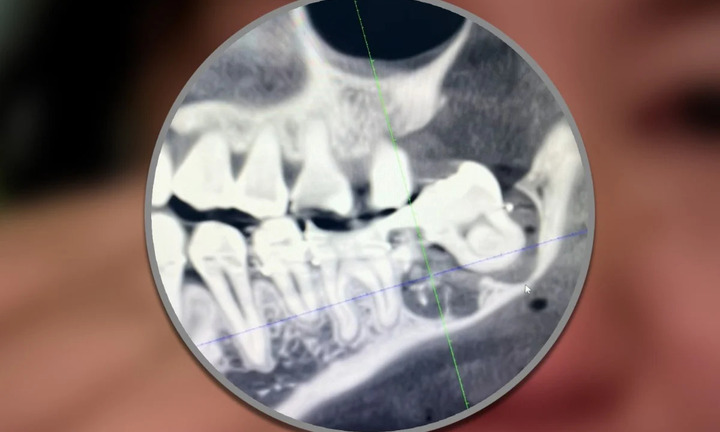

Người phụ nữ nhảy lầu tại bệnh viện sau khi bị nhổ nhầm răng khôn

Cô Wu bất lực trong việc cáo buộc bác sỹ nhổ nhầm chiếc răng khỏe rồi gắn lại khiến cô đau đớn cùng cực; 5 ngày sau cô nhảy từ tầng 11 của bệnh viện và qua đời.

Mọc răng khôn được coi là nỗi sợ của mỗi người vì cảm giác khó chịu mà nó đem lại.

Điều đáng sợ nhất của việc nhổ răng khôn là cảm giác đau, khó chịu của những ngày sau đó, nhưng việc chăm sóc vết thương tốt sẽ đẩy nhanh sự hồi phục.

Các chuyên gia cho biết, răng khôn khi mọc lệch có thể gây nhiều biến chứng nguy hiểm tới tính mạng.

Mới đây, một nữ bệnh nhân ở Quảng Ninh qua đời nghi do sốc phản vệ trong khi nhổ răng số 8 xôn xao dư luận, vậy răng số 8 là răng gì?